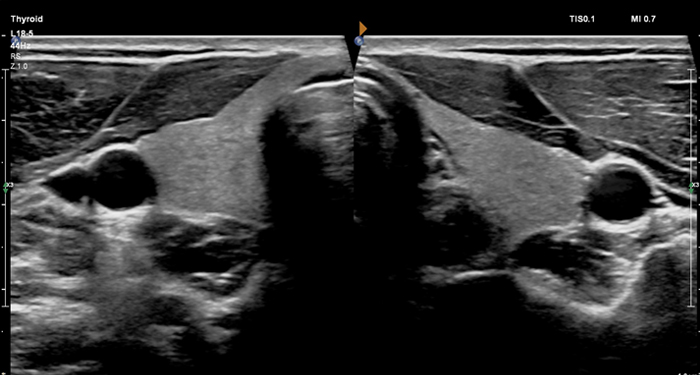

At the touch of a button, the new MaxVue high-definition display brings extraordinary visualisation of anatomy with 1,179,648 additional image pixels compared to a standard 4:3 display format mode. MaxVue enhances ultrasound viewing during interventional procedures and provides 38% more viewing area to optimise the display of dual, side/side, biplane, and scrolling imaging modes.

MaxVue offers a 38% greater viewing area.

MaxVue offers 1,179,648 additional image pixels compared to a standard 4:3 display format mode.